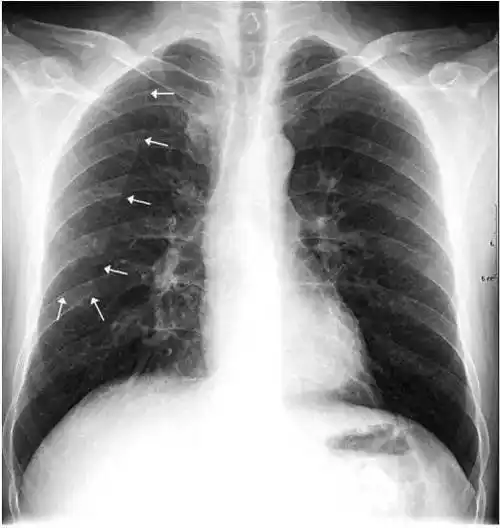

影像解剖入门正常胸片怎么看